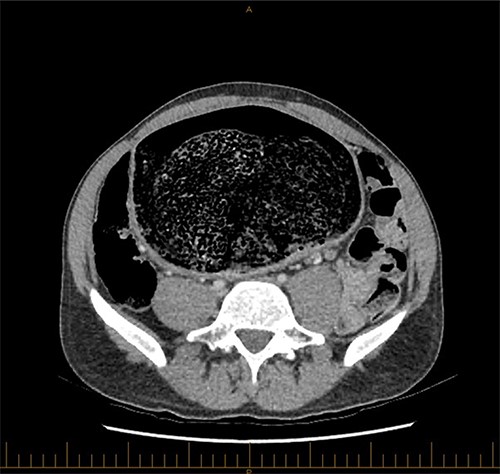

A 28-year-old gentleman self-presented to the emergency department with profuse overflow diarrhea and vomiting. The patient reported he had normal bowel motion until the morning of presentation. He denied any abdominal pain. On examination, the patient appeared pale, diaphoretic and dehydrated. His abdomen was grossly distended, however, was nontender. He was afebrile yet experienced sustained sinus tachycardia to a rate of 120 beats per minute. His blood pressure sat at 96/75 mmHg and was tachypneic to a respiratory rate of 30 and was saturating at 96% on room air. His blood tests showed a leukocytosis to 31, severe metabolic acidosis pH 7.18, lactate 7.7 and hyperkalemia K 6.0 estimated glomerular filtration rate (eGFR) of 68 mL/min/1.73 m2 and a creatinine count of 125μmol/L The computed tomography imaging of his abdomen revealed a massively dilated rectum and sigmoid colon extending to his splenic flexure without evidence of a perforation (Figs 1 and 2). Plain film radiography shows a sizeable faecaloma in the sigmoid colon (Fig. 3).

Coronal view of a CT image of a large faecaloma in the sigmoid.